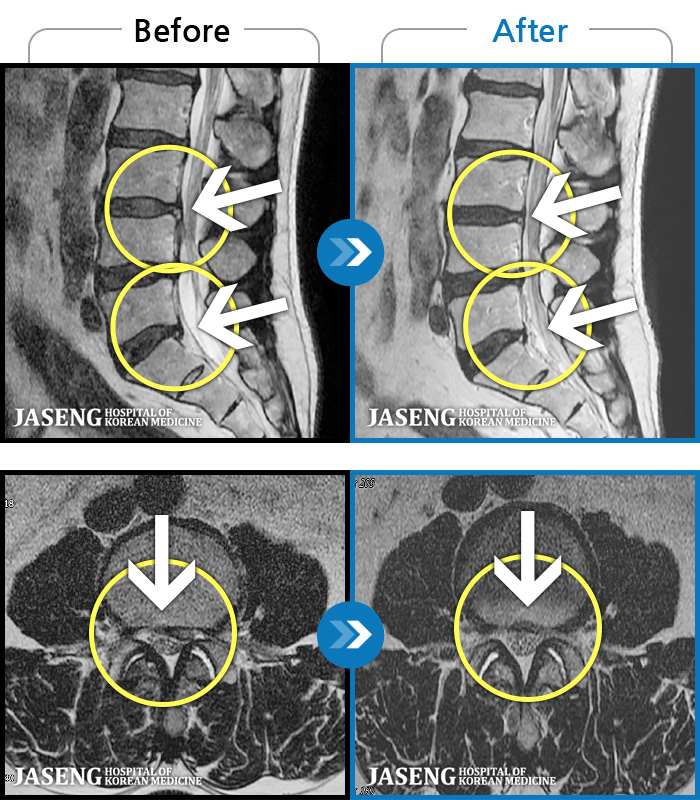

- MRI ġ

MRI ġ

56 MRI ũ ʸ Ȯϼ.

[õ_㸮ũ] ߲ 㸮 , ٷ